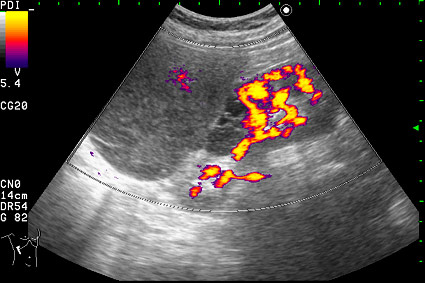

Сонограмма правой почки.

Образование в режиме энергетического доплера.

Нет, это кистоподобное образование, связанное с почкой.

Необычнвя картинка. В голову приходят самые "сумашедшие" предположения (в т.ч. малигнизация кисты, но нет кровотока, нагноившаяся киста, но нет реакции ее стенки; киста с густым содержимым, но отчего оно так загустело?). Просветите нас, пожалуйста.

Почечно-клеточный рак правой почки, кистозная форма.

Но только по густому содержимому кистозного компонента. Стенка тонкая, кровоток не прокрашивается (единичный мелкий срез сосуда в центре образования больше похож на артефакт, а м.б. им и является).

Если бы в этом случае и содержимое было бы более "жидким", вероятность постановки правильного диагноза была бы минимальной.

Я в своем заключении предположил кисту с внутренним кровоизлиянием.

И ошибся.